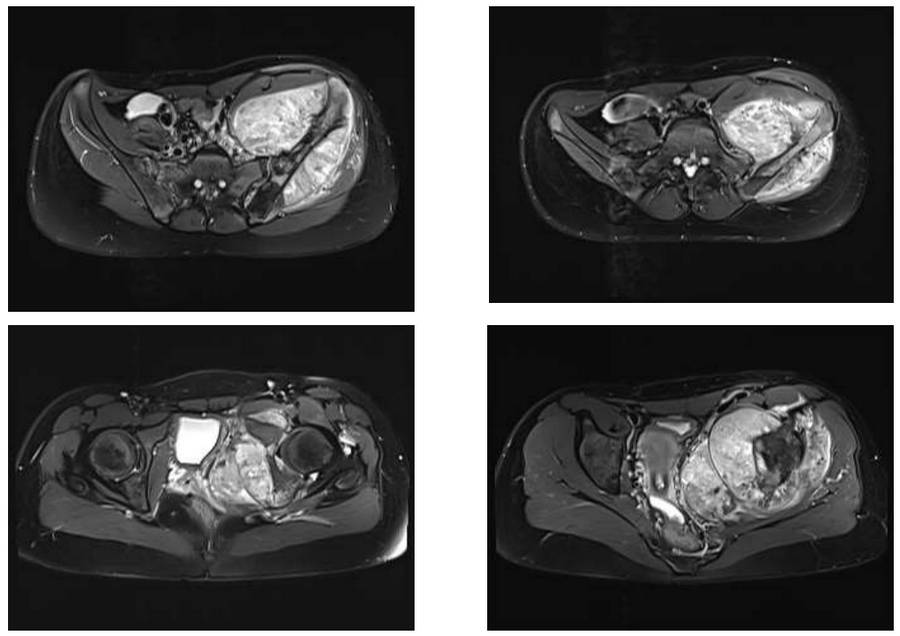

Before the surgery: The MRI shows a large tumor tissue that has caused bone destruction affecting the entire 5th lumbar vertebra, sacrum, and iliac crest, and extending into the soft tissue.